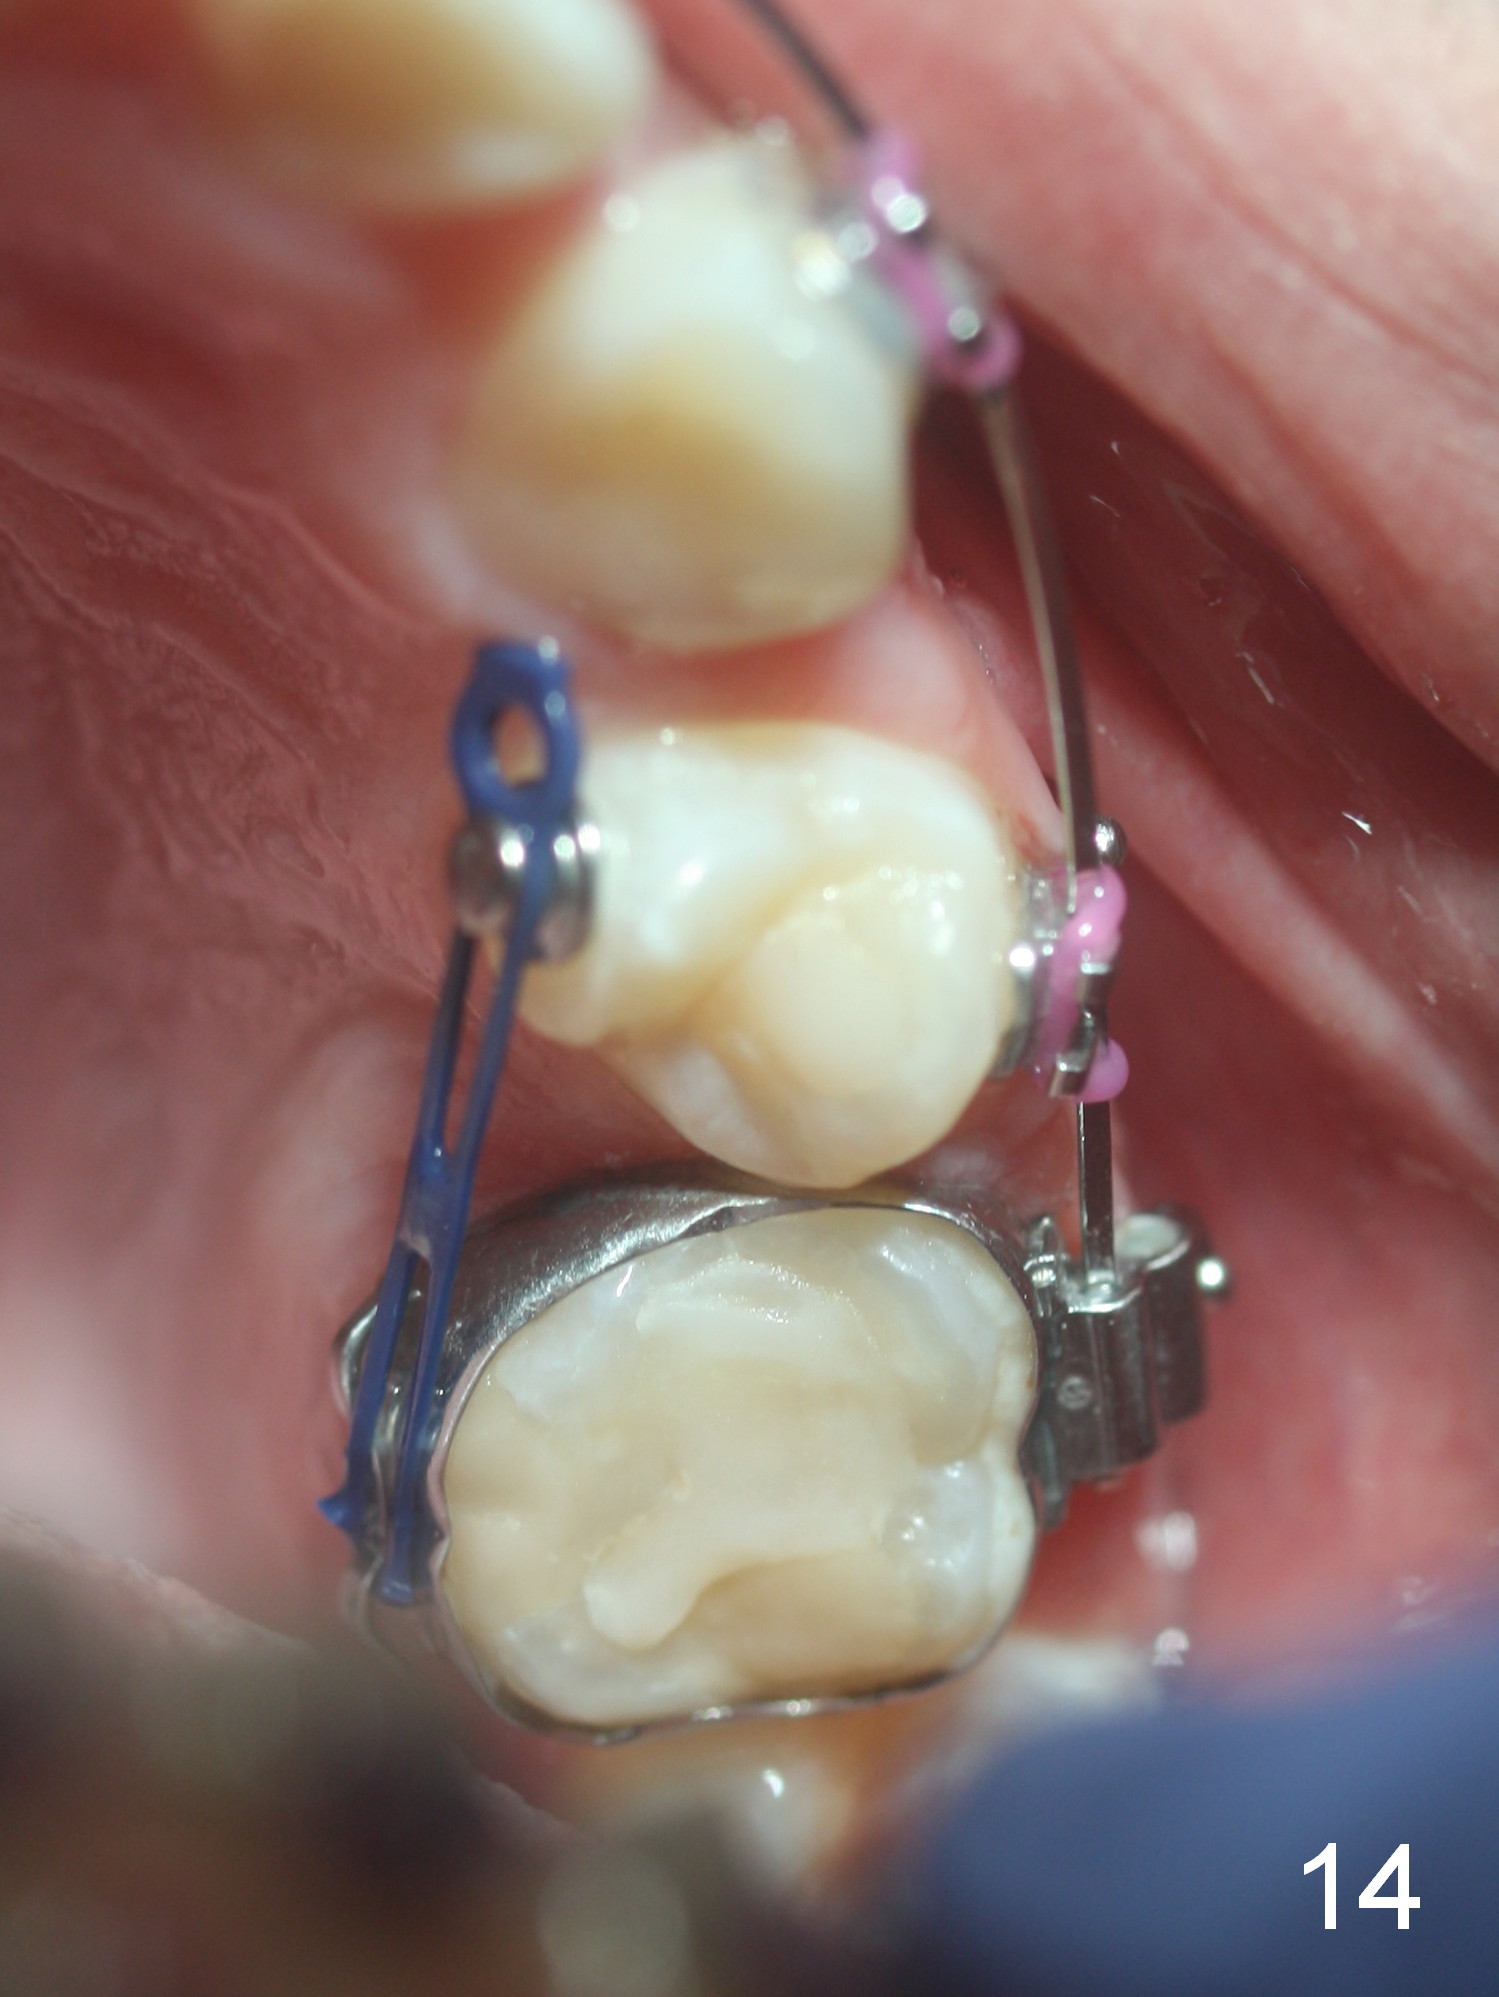

Approximately 4.5 months of power chains between 4s and 6s buccally, U4s contact U6s with rotation (Fig.13,14), while L4s have 1-2 mm to be distalized (Fig.15,16). With placement of lingual buttons on U4s and power chains lingually, the rotation should be corrected. The rotation wedges were placed with ligature wire on the left in the last visit. The patient returns 3 weeks later.